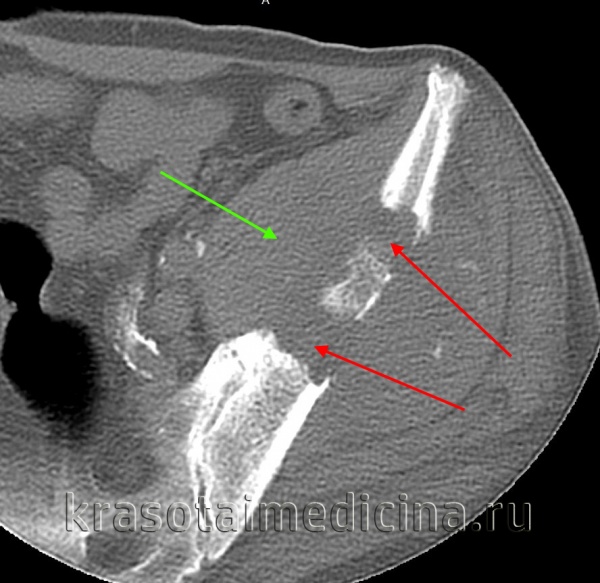

КТ левого бедра. Объемное образование (оссифицированная энхондрома) в нижней трети диафиза бедренной кости.

КТ таза. Метастатическая карцинома подвздошной кости слева с деструкцией костной ткани (красная стрелка) и обширным мягкоктанным компонентом (зеленая стрелка)